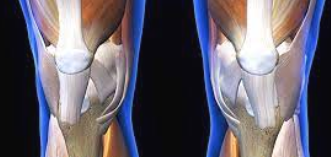

무릎 연골 손상의 주요 증상

연골 손상 정도별 증상 변화

1단계: 경미한 연골 손상 증상

연골 손상 초기 단계에서는 증상이 미미하여 단순한 피로나 근육통으로 오인하기 쉽습니다. 주요 증상으로는 운동 후 가벼운 무릎 불편감, 아침 기상 시 약간의 강직감, 날씨 변화에 따른 무릎 불편감 등이 있습니다.

이 단계에서는 일상생활에 큰 지장이 없어 대부분 간과하게 되지만, 적절한 관리가 이루어지지 않으면 손상이 진행될 수 있습니다. 따라서 가벼운 증상이라도 지속되면 전문의 상담을 받는 것이 중요합니다.